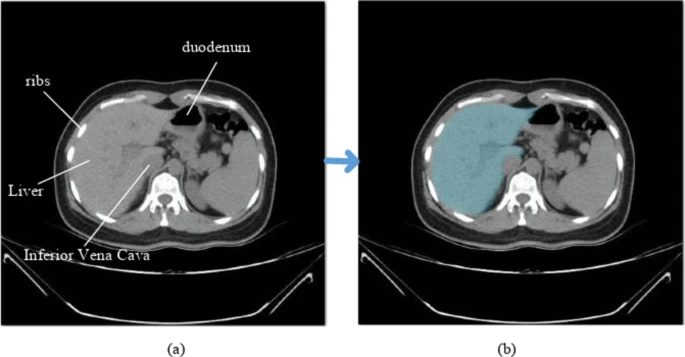

A Look at Liver Segmentation (Source)

Medical annotation isn’t limited to flat images. CT and MRI scans often produce three-dimensional data, in which structures have to be labeled across multiple slices.

Annotated 3D scans help AI models support earlier cancer detection and more accurate assessments. For instance, in some hospitals, models trained on labeled kidney CT scans are being used to assist radiologists in identifying tumors and help surgeons plan procedures more efficiently.